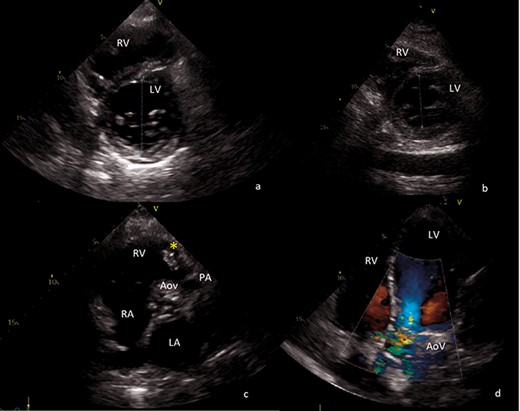

Severe PV insufficiency, with a single sizable vegetation of about 4 cm provoking right ventricular outflow obstruction (Fig. 1c)

Transthoracic echocardiography images. (a) Preoperative short axis view of left ventricle. End-diastolic left ventricle diameter of 68 mm. (b) Postoperative short axis view of left ventricle. End-diastolic left ventricle diameter of 43 mm. (c) Sizable vegetation (yellow asterisk) of about 4 cm provoking right ventricular outflow obstruction. (d) Four-chamber view, showing severe aortic regurgitation. AoV aortic valve; LA left atrium; LV left ventricle; PA pulmonary artery; RA right atrium; RV right ventricle.